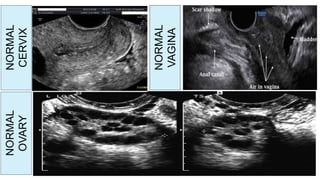

NORMAL

UTERUS

ENDOMETRIUM

NORMALOVARY

CERVIX

OVARY

VAGINA